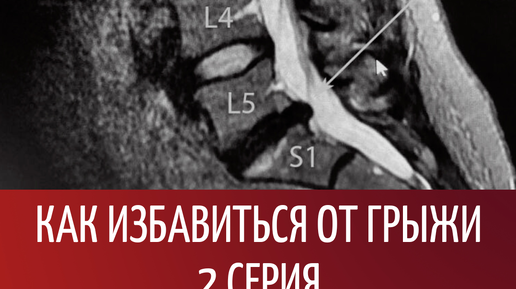

Как избавиться от грыжи за 12 недель. 2 серия